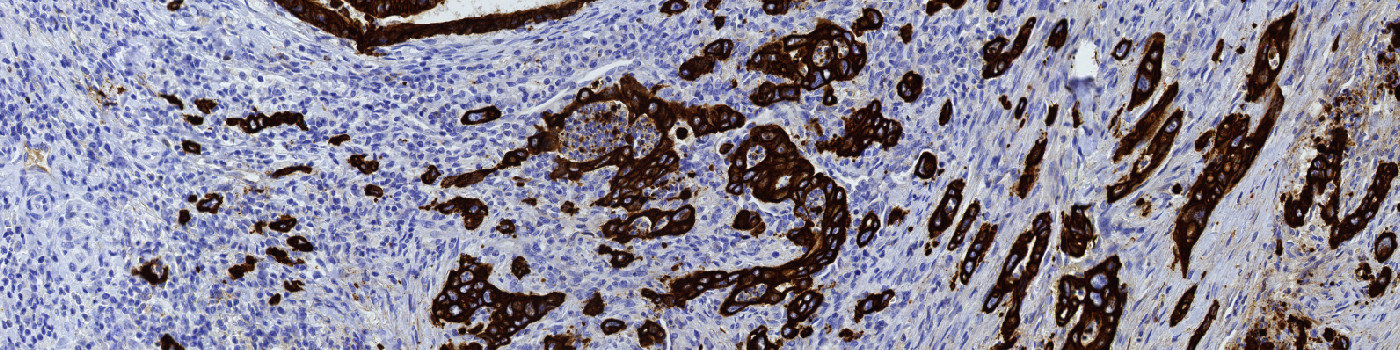

Figure 1

Colon tissue where the invasive front of colorectal cancer is manually marked (green ROI).